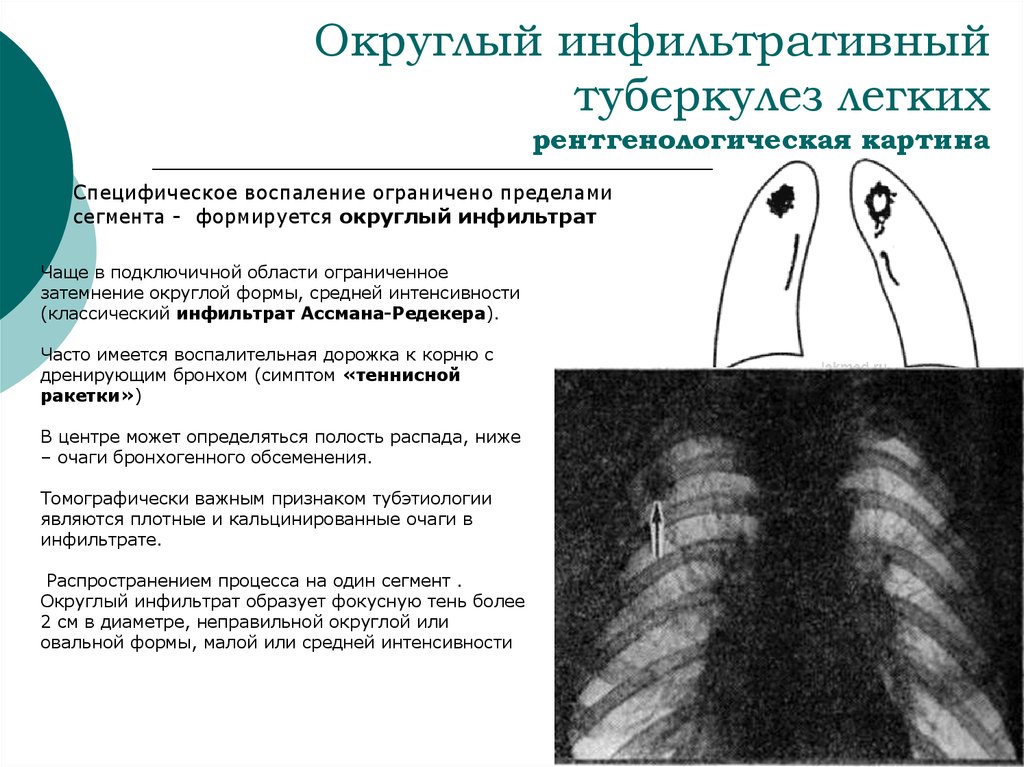

Иллюстрации по теме очагового и инфильтративного туберкулеза